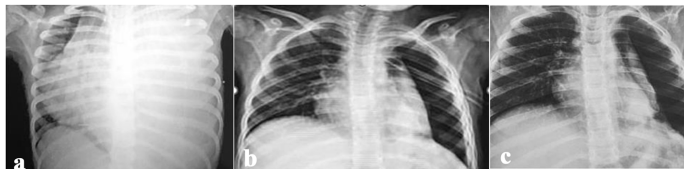

血培养、胸水培养和痰培养阳性率分别为17%、23%和18%,MRSA在胸水培养阳性株中占比达42%。值得注意的是,3例纤溶治疗后快速进展为NP的病例,其初始CT均显示严重实变伴高度分隔性积液。